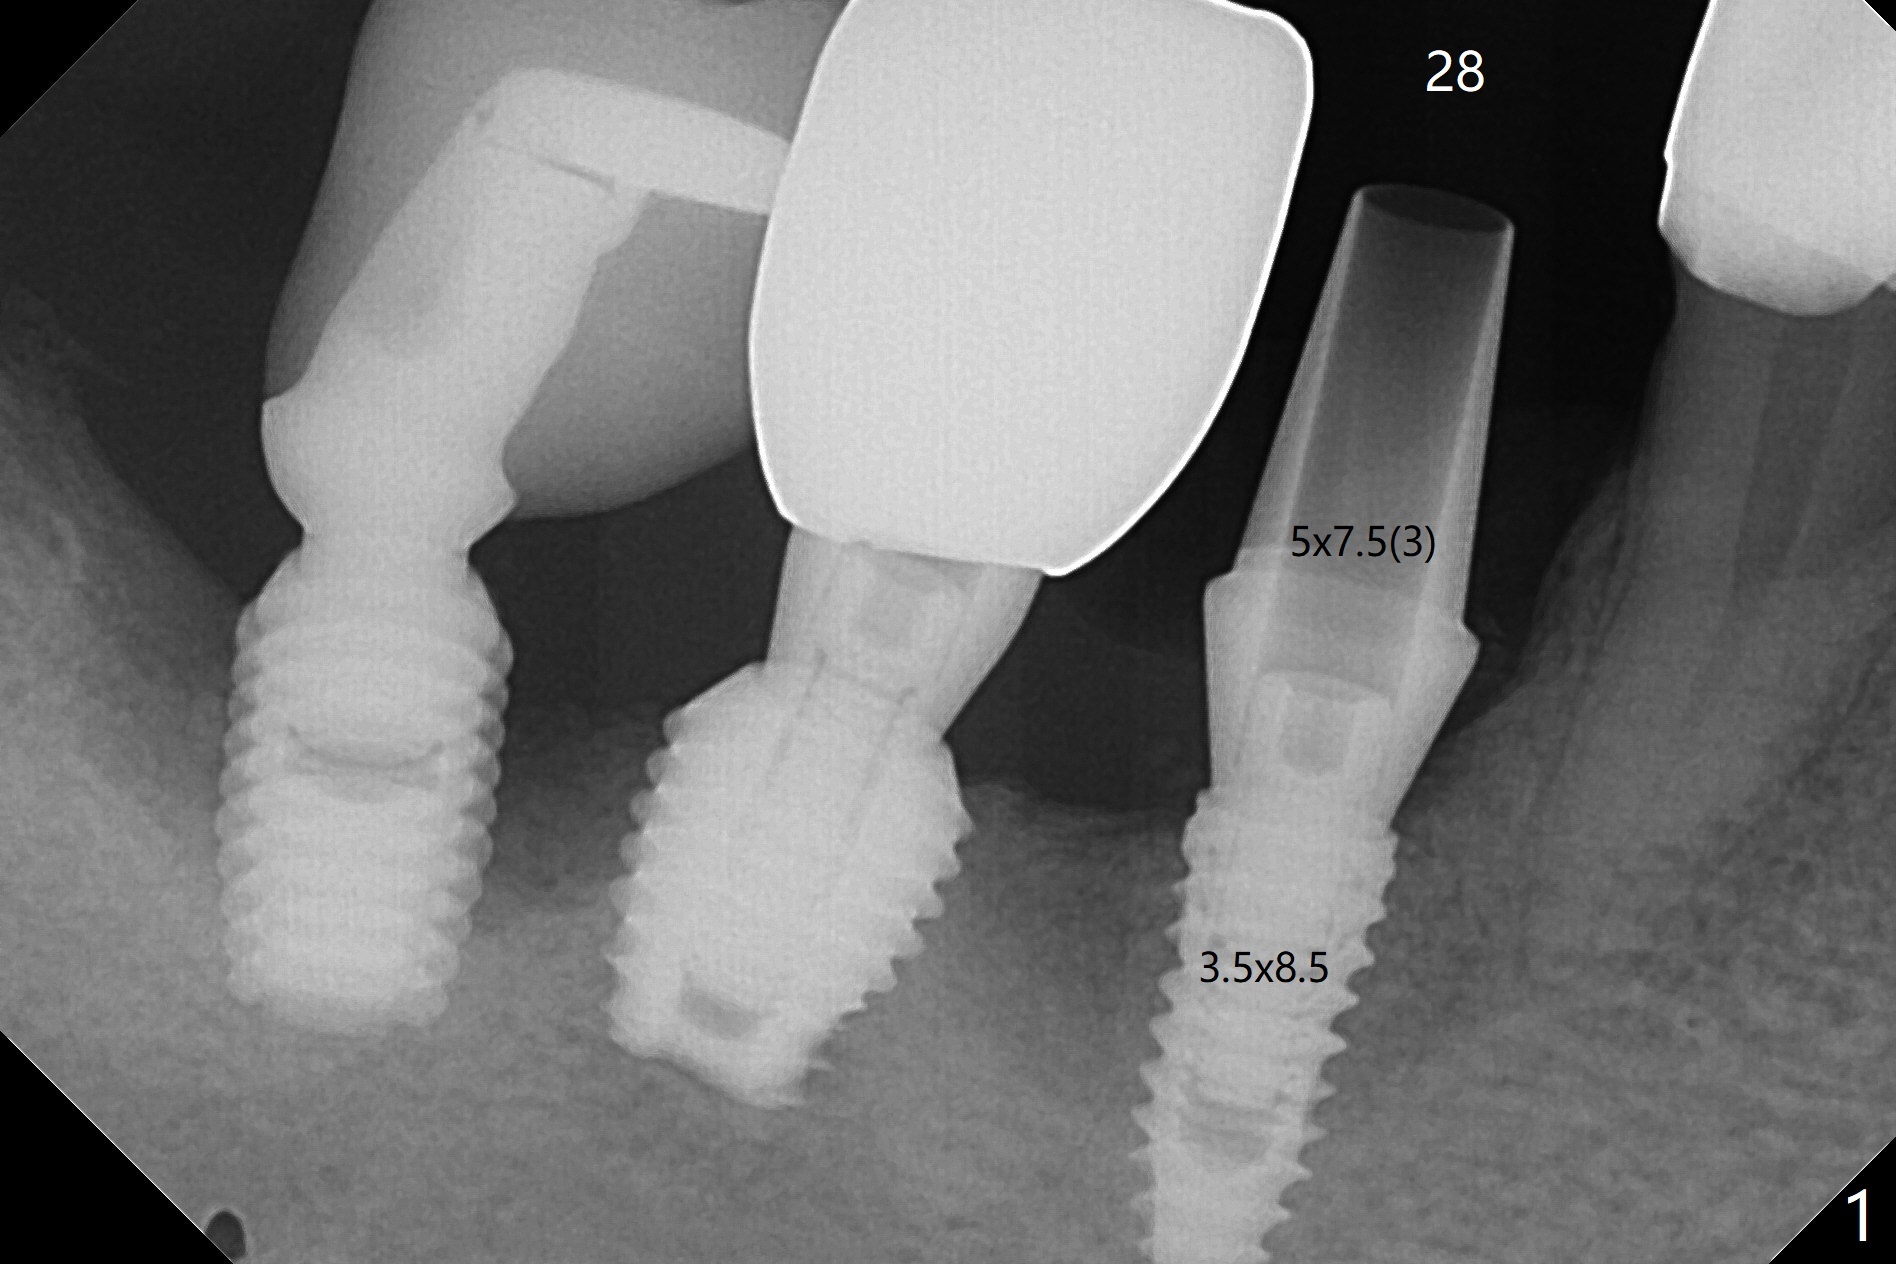

28牙位3.5x8.5毫米植体导板植入后,颊侧远中螺纹暴露,为了植骨,附近骨壁钻洞创造出血点以及放置基台(图一:5x7.5(3)毫米)。放置粘性骨粉后(图二:*),覆盖薄层PRF,后者可能很快吸收,为了防止骨粉暴露,放置不可吸收膜(图三:*),当中打洞,穿过基台固定,表面缝合。术后六周不可吸收膜部分暴露(图四)。图五,六显示在取出时膜当中固定用的洞,下面伤口愈合正常(图七)。